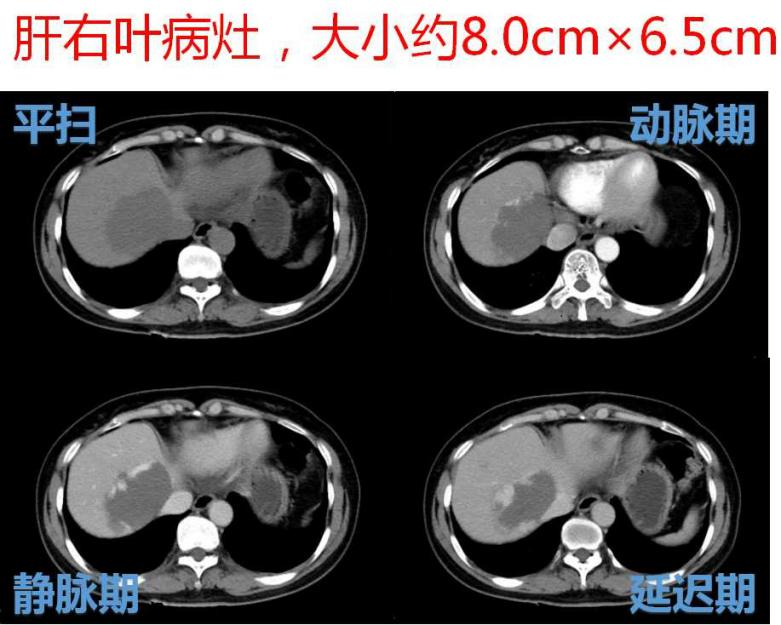

日前, 微创介入科为一名肝内多发大血管瘤患者实施肝动脉介入栓塞术,轻松解决了患者的疾病所带来的痛苦和精神压力,术后患者腹痛及腹胀等症状基本缓解,生活质量得到了明显提高。此项技术安全有效。该患者为一名中年女性,因上腹部隐痛伴腹胀行腹部CT检查,发现肝内多发血管瘤,其中最大2处病灶大小分别为8.0cm×6.5cm、7.0cm×5.6cm。

DSA造影示:肝左、右动脉明显增粗,肝左、右叶可见多发充填式片状及结节状爆米花样强化血管湖,呈弥漫性分布。静脉期门静脉主干显影尚可。